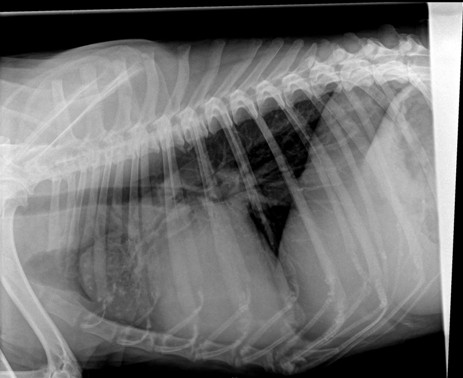

Ania hatte uns darum gebeten, mit Dario zur Klinik fahren zu dürfen, da er Probleme mit einem dicken Gelenk am Hinterlauf hatte. Am 12.01.17 war Ania mit ihm in der Tierklinik,

wo er untersucht und geröntgt worden war. Die Röntgenaufnahmen haben leider ein stark vergrößertes Herz gezeigt, sowie den Verdacht auf Knochentumor ergeben. Zur Sicherheit

wurde ein weiterer TA konsultiert, der die Diagnose leider bestätigte und zudem auch noch

einen Lungentumor diagnostizierte. Die Ärzte rieten dringend zur Euthanasie.